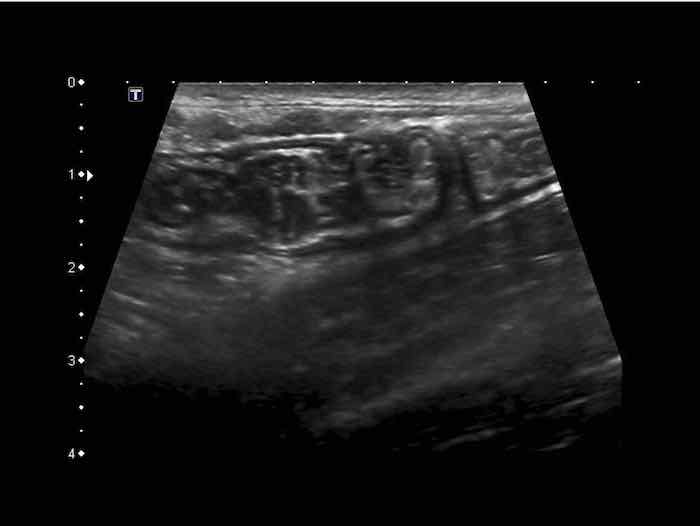

Hình ảnh siêu âm kinh điển của lồng ruột hồi-manh tràng ở hai trẻ khác nhau.

Trong cả hai trường hợp, đoạn hồi tràng bị lồng được định vị không đối xứng bên trong ống lồng ngoài, do mạc treo ruột tăng âm có chứa mỡ, bám vào hồi tràng và đi theo hồi tràng khi bị kéo vào trong.

Trong mạc treo, siêu âm cho thấy một hạch bạch huyết mạc treo (hbh) phóng đại ở cả hai.

Các hạch này phì đại như một phần của tình trạng tăng sản hạch bạch huyết toàn thân và khônghu trú trong lòng hồi tràng.

Do đó đây không phải là điểm dẫn đầu nguyên phát. Ở bệnh nhân bên phải, ruột thừa (mũi tên) cũng bị kéo vào trong.

Lưu ý cấu trúc đa lớp của thành bụng phía trước của phức hợp lồng ruột, đại diện cho ba lớp thành ruột bị gấp lại.